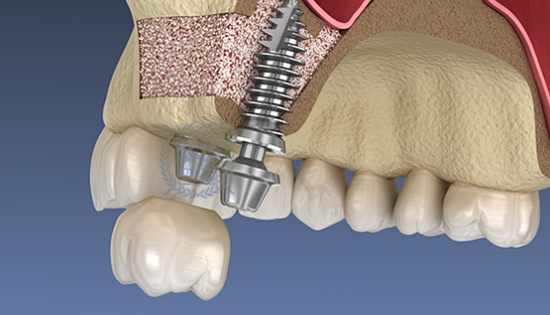

뼈이식 / 임플란트 식립공간 확보

잇몸을 절개하고 난 후 뼈를 넣고 상악동을 들어 올릴만한 작은 통로를 만들어 뼈이식할 공간과 임플란트 식립할 공간을 확보합니다.

잇몸 뼈이식 시술 진행

들어올린 빈 공간에 뼈를 이식하는데 이때 사용되는 뼈이식 재로로는 자가치아뼈, 자가골, 인공뼈, 합성골 등이 있습니다.

임플란트 매식체 식립

잔존하고 있는 잇몸뼈의 양에 따라 뼈이식과 동시에 임플란트 식립하기도 하고 6-9개월 후 식립하기도 합니다.